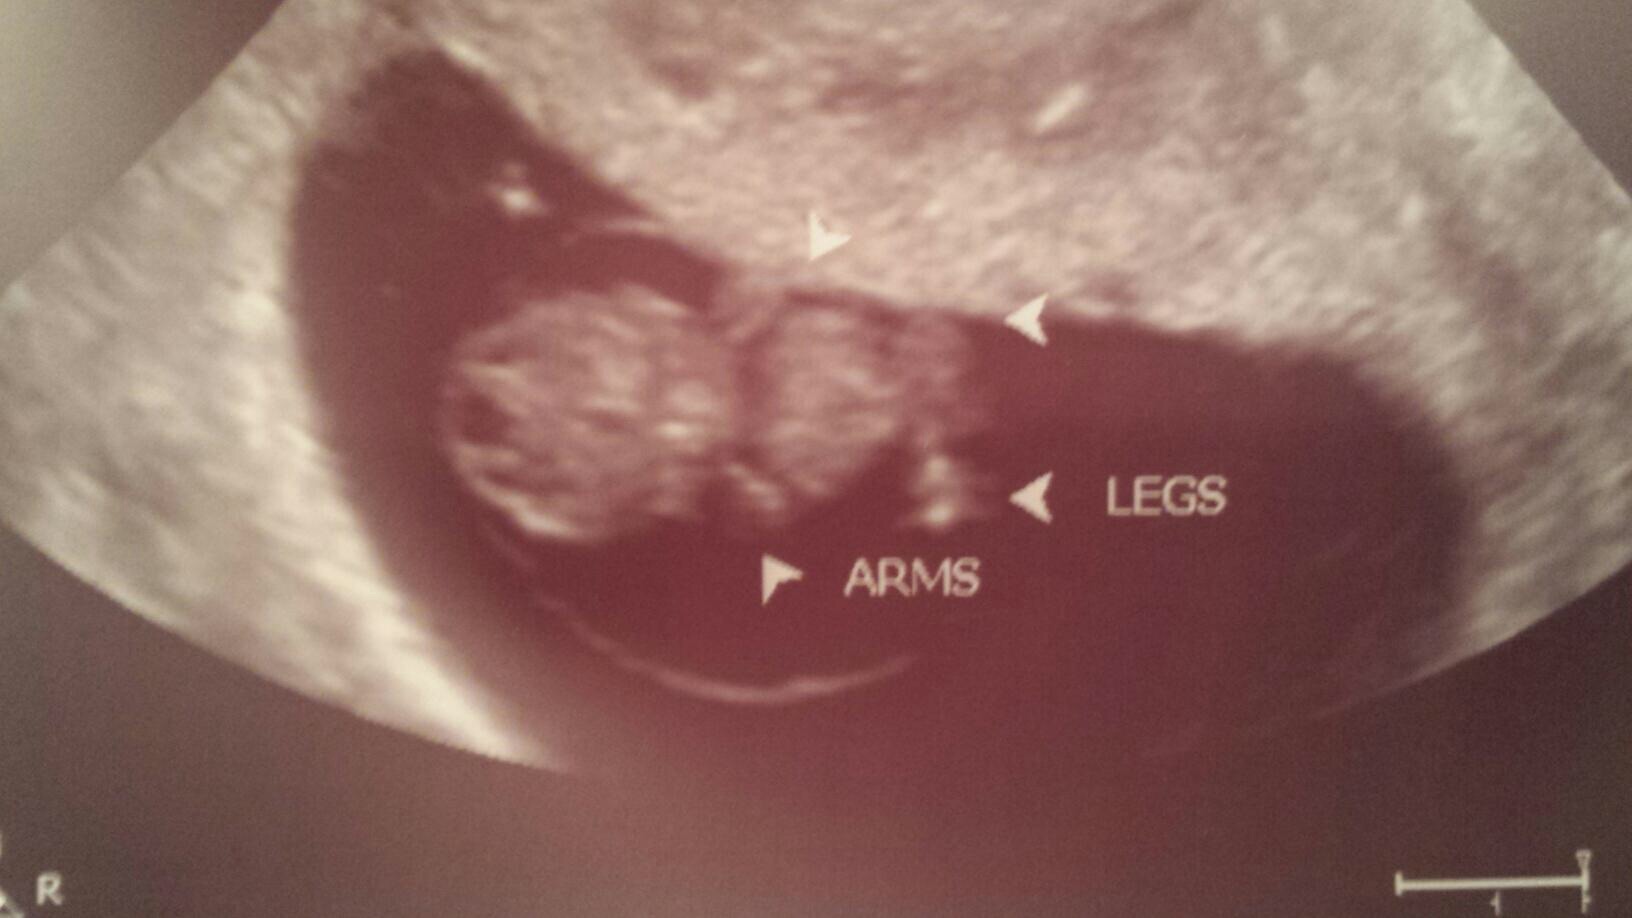

Our 10 week scan that we had this last Tuesday 4/7. Baby measured 10w5d with a heartbeat of 160 bpm. It was a great day for husband and I, not to mention how adorable those little wiggle wiggles were. omgosh, just melted my heart. I am so in love